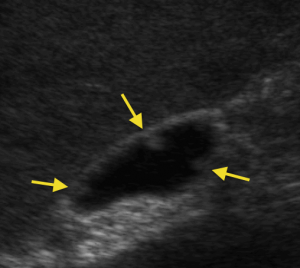

How are gallstones diagnosed?When gallstones are suspected, the first test to be done is an abdominal ultrasound. This is a simple, fairly painless and straightforward test, and does not involve the use of x-rays. Ultrasound waves are used to create images of organs and if stones are present, the sound waves will bounce off them and show them up (see illustration).

Occasionally, other tests may be required, such as an MRI scan (referred to as MR cholangio-pancreatography or MRCP), CT scan, or radio-isotope tests such as HIDA scans. An MRCP will show the anatomy of the liver and the gall bladder, the bile duct, as well the surrounding organs such as the pancreas (see illustration).